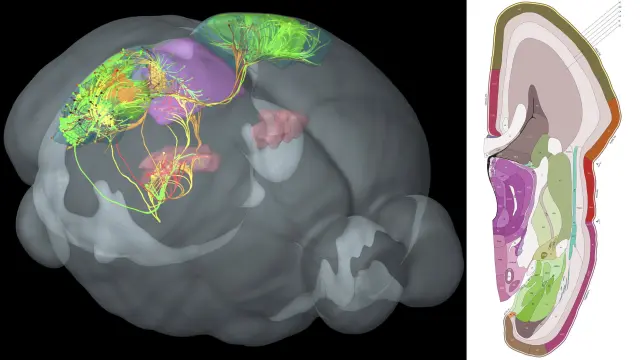

La actividad cerebral asociada con la empatía no estaba arraigada en una parte del cerebro, la forma en que las entradas sensoriales tiende a ser procesadas. Más bien, se extendió a través del cerebro e involucró múltiples regiones cerebrales. "El cerebro no es un sistema modular donde hay una región que maneja la empatía --describe Wager--. Es un proceso distribuido".

Los patrones asociados con la preocupación empática, por ejemplo, se superponen con sistemas en el cerebro asociados con valor y recompensa, como la corteza prefrontal ventromedial y la corteza orbitofrontal medial. En contraste, patrones de angustia empática se superponen con sistemas en el cerebro conocidos por reflejar, como la corteza premotora y las áreas corticales somatosensoriales primarias y secundarias, que ayudan a un individuo a simular o imaginar lo que otra persona está sintiendo o pensando.